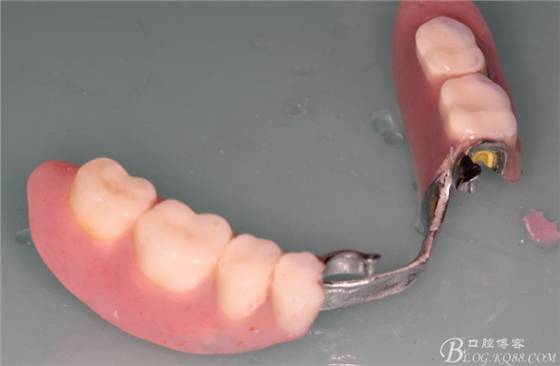

下頜由于44治療之后,松動(dòng)度改善不大,原來的咬合創(chuàng)傷比較大,不能承擔(dān)較大的(牙合)力,選擇覆蓋義齒,把它磨短平齊牙齦,

其他牙比較集中,選擇雙端球帽式附著體修復(fù)雙端游離缺失

44作為覆蓋基牙保留完好,牙周狀態(tài)良好,附著體基牙有一定的牙齦萎縮,

下頜附著體 義齒有菌斑殘留